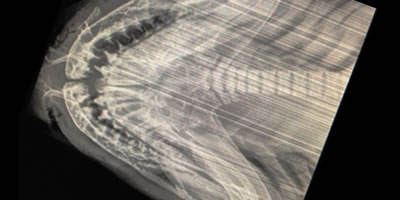

The skeleton of elasmobranchs is made of cartilage. Vestigial ribs give no support.

- The skeleton may be partially calcified to some extent with calcium phosphates and carbonates, particularly in the vertebral column. The calcified cartilage is not a true bone.

- A shark's cranium is a single compact cartilaginous block which encloses the brain, olfactory, and auditory capsules. Jaws are loosely attached to it.